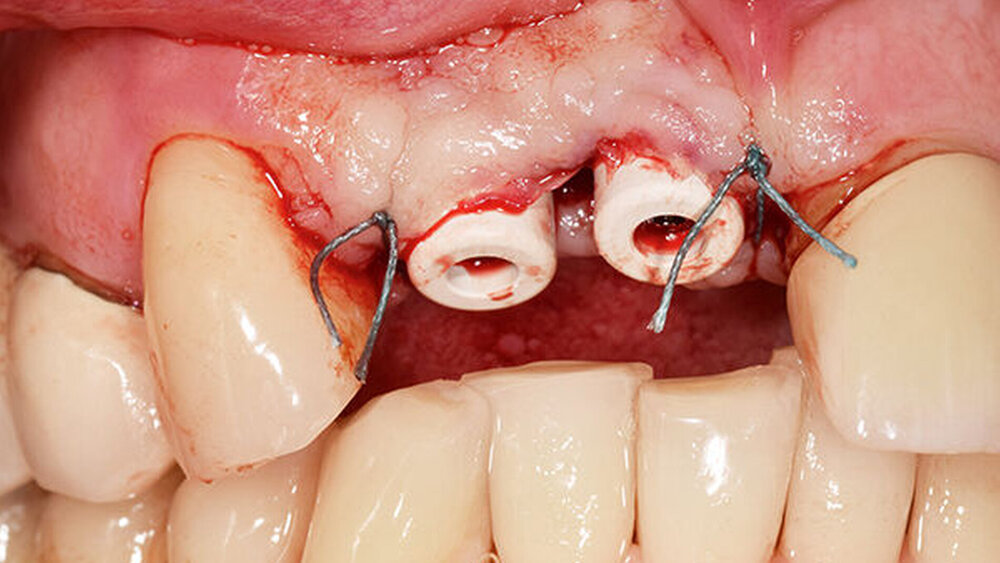

Während der komplikationslosen Heilungsphase betreute der Hauszahnarzt den Patienten. Wie geplant, erfolgte nach zwölf Wochen die Implantatfreilegung (Abb. 9) in unserer Praxis. Das Weichgewebe zeigte sich in einem blutungs- und reizfreien Zustand. Mit einer leicht palatinal orientierten crestalen Kieferkammschnittführung wurden die Implantate freigelegt, das Weichgewebe wurde nach vestibulär verdrängt (Abb. 10) und die Gingivaformer wurden aufgesetzt. Um einen quantitativen Zugewinn von keratinisiertem Gewebe zu erhalten, wurde die Naht zwischen den Implantaten nicht komplett geschlossen. Die Implantate zeigten sich klinisch und röntgenologisch sicher osseointegriert (Abb. 11).